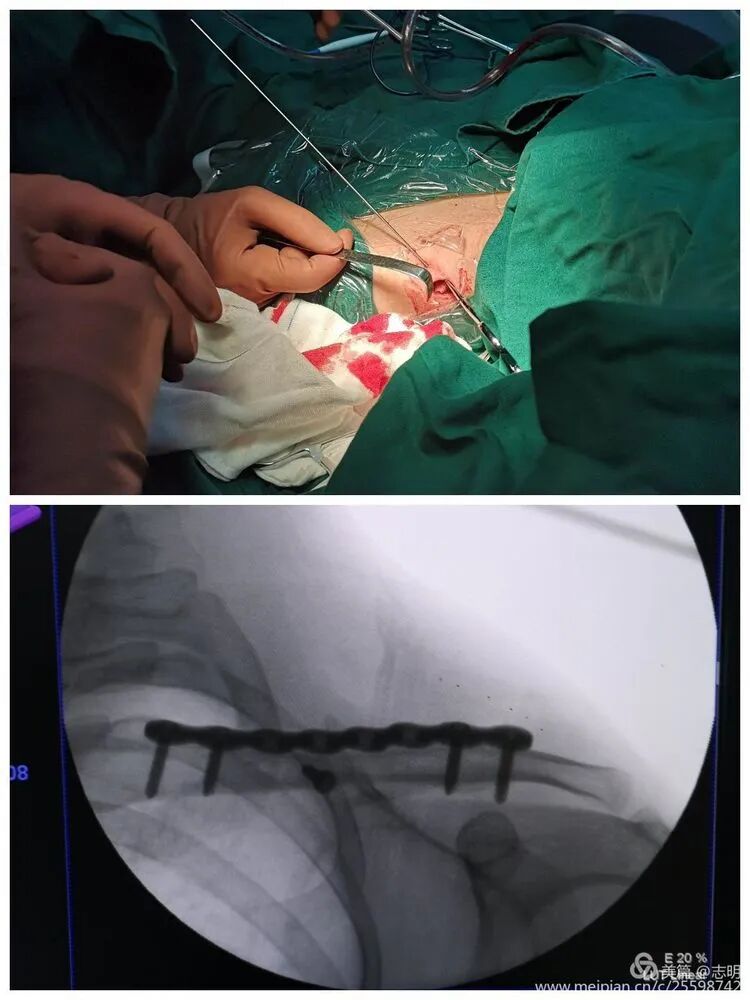

(This image shows a percutaneous tool, possibly for tunneling or reduction assistance).

(Image likely illustrating an instrument used for tunneling or manipulating fragments percutaneously).

(Clinical image showing surgeon's hands manipulating the shoulder, likely assisting in reduction).